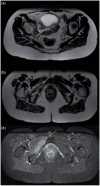

The purpose of this article is to familiarize the reader with the anatomy of the major pelvic nerves and the clinical features of associated lumbosacral plexopathies. To demonstrate this we illustrate several cases of malignant lumbosacral plexopathy on computed tomography, magnetic resonance imaging, and positron emission tomography/computed tomography. A new lumbosacral plexopathy in a patient with a prior history of abdominal or pelvic malignancy is usually of malignant etiology. Biopsies may be required to definitively differentiate tumour from posttreatment fibrosis, and in cases of inconclusive sampling or where biopsies are not possible, follow-up imaging may be necessary. In view of the complexity of clinical findings often confounded by a history of prior surgery and/or radiotherapy, a multidisciplinary approach between oncologists, neurologists, and radiologists is often required for what can be a diagnostic challenge.